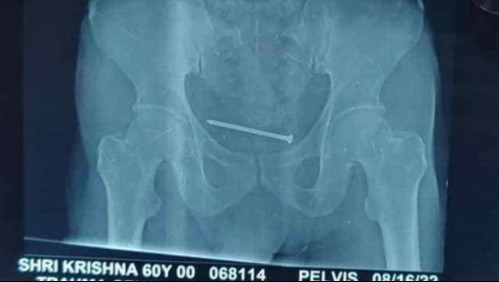

Mundo Tenía un "dolor insoportable" y los doctores terminaron encontrando un clavo de 10 centímetros en su vejiga